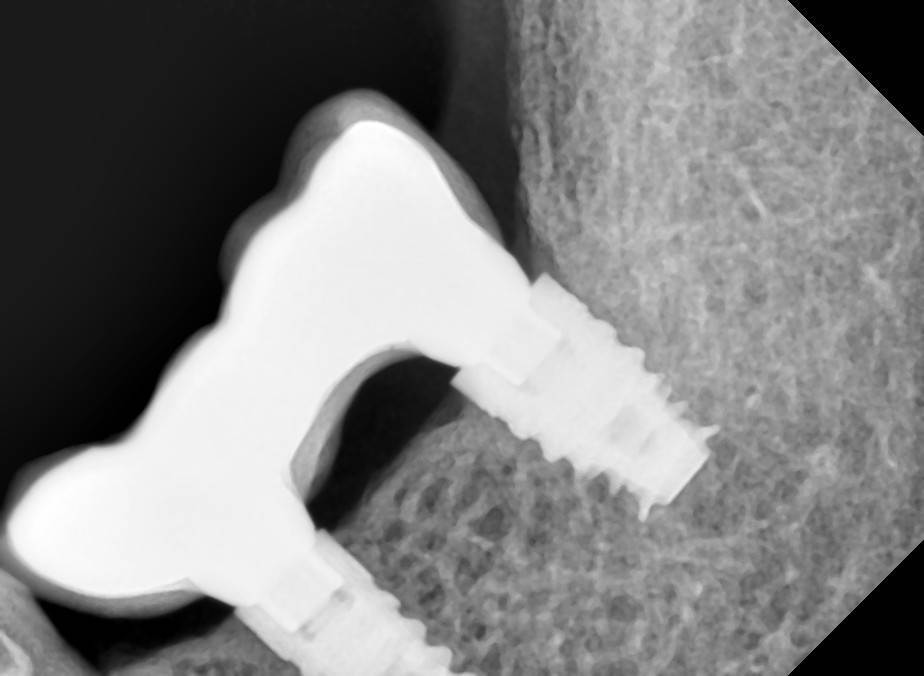

Aquarius Опубликовано 27 мая, 2022 Поделиться Опубликовано 27 мая, 2022 (изменено) 2016 г - установка имплантов. В то время находился под впечатлением от исследований Карлоса по гиперторку. Дал под сотню на дистальном импланте . Потом сильно пожалел))) Второй снимок - спустя 4 года на осмотре. https://wampi.ru/image/RZ3XaNg https://wampi.ru/image/RZ3XLcn Изменено 27 мая, 2022 пользователем Aquarius Ссылка на комментарий

Aquarius Опубликовано 28 мая, 2022 Поделиться Опубликовано 28 мая, 2022 (изменено) Ага, сам не понимаю почему. Аж в аппроксималку кость полезла . Несмотря на огрехи в протетике . И ни о каком остеоиде здесь речи быть не может. Вдобавок хирургия без каких-либо наворотов в виде ССТ и т.д. Трофика при нагрузке, единственное объяснение Изменено 28 мая, 2022 пользователем Aquarius Ссылка на комментарий